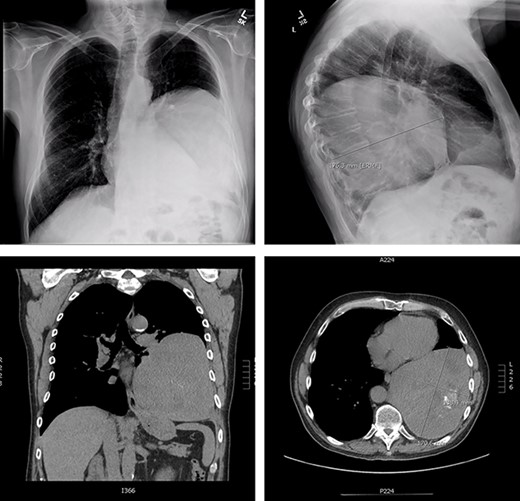

The patient is a 70-year-old man with a 75-pack-year smoking history and occupational asbestos exposure, who presented with back pain and constitutional symptoms in 2019. Physical exam was unremarkable except for hypertrophic pulmonary osteoarthropathy with digital clubbing. Computed tomography chest demonstrated a 18.3 × 17.0 × 13.8 cm left pleural-based tumour, with heterogeneous density and internal calcifications, resulting in compression of the left lower bronchi (Fig. 1). The patient’s medical records revealed that he was originally diagnosed with a left-side pleural SFT in 2013 (Fig. 2); imaging and biopsy at that time revealed a 9.3 cm spindle cell tumour consistent with SFT. The patient was lost to follow-up.

Representation of solitary fibrous tumour in 2019 showing 18.3 × 17.0 × 13.8 cm left-sided pleural-based tumour.

Initial presentation of solitary fibrous tumour in 2013 showing 9.3 × 6.1 cm left-sided pleural-based tumour.